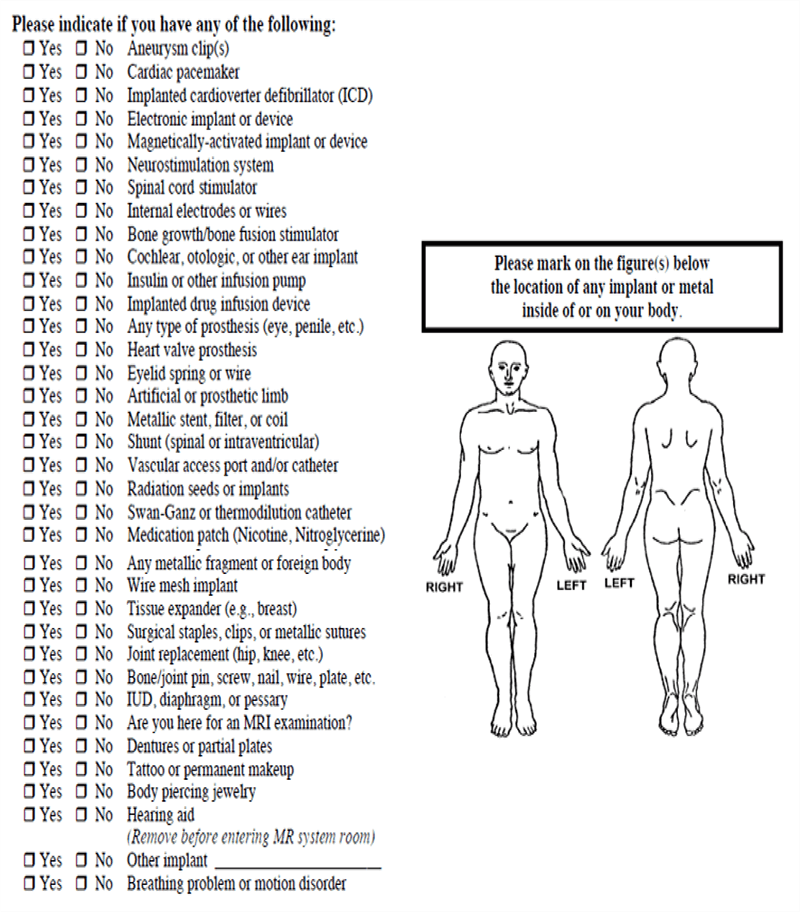

When the scheduled date arrives, the patient arrives for their MRI and is given a more detailed screening form. Patients are usually required to sign these screening forms to attest to the correctness of the information. The screening form will repeat the questions done at pre-screening, but now this is a signed copy of those responses. Some questions on the screening form give information about other tests that have been done and information to help with the diagnosis of this exam.

The technologist then checks this screening form to make sure there is nothing that requires additional information is needed for clarity. If all goes well, everything had been taken care of at Pre-screening and the patient is ready to move on for the scan. Take a few moments to look at this example of a screening form and the types of questions that are asked.

This is the back of a typical screening form. Notice how many times and how many different ways some of the questions are asked. This is done to provide a thorough screening and to NOT have any issues with miscommunication or misunderstanding.

As an example, a patient might have a defibrillator in place, rather than the usual pacemaker/defibrillator. If the screening form was to only ask about pacemakers, a patient may think their defibrillator is ok. Some patients may feel that if something has been inside them for 20 years it is not relevant. And a patient with a bladder stimulator that is no longer functional may not find it important to reveal that it is in place because it no longer works.

A best safety practice would be to follow-up at the end by asking if the patient they have ever had any medical devices implanted in their body.